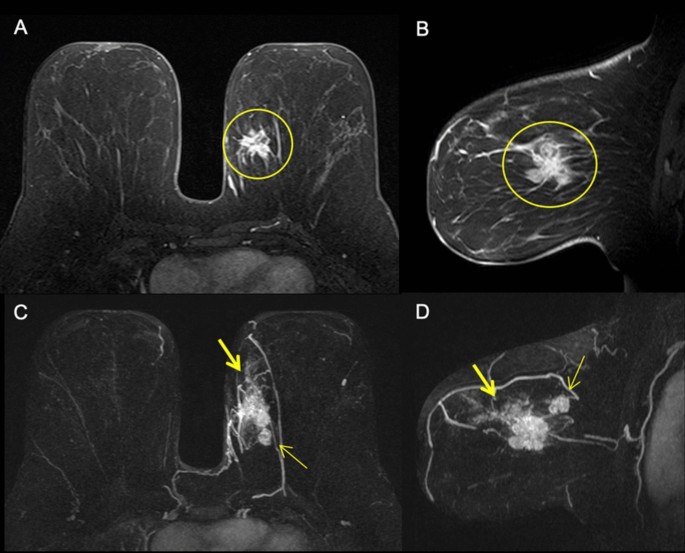

The correlation between MRI features and tumour immunophenotype revealed significant associations with mass shape, margins, internal enhancement and delayed phase of the kinetic curve (Table 2). Oval or round shape and rim enhancement were most frequently observed in triple-negative and luminal ER-low-positive tumours (Fig. 2). Spiculated margins were most frequent in luminal A and luminal B tumours (Fig. 3). A persistent kinetic curve was more frequent in luminal A tumours, while a washout curve was more common in triple-negative, HER2-overexpressing and luminal ER-low-positive immunophenotypes (Fig. 4).

Our results show that luminal ER-low-positive tumours have similar imaging characteristics to triple-negative breast cancer, including similar lesion presentation and mass features (shape, margins, enhancement and late kinetic curve). A round or oval unifocal mass with circumscribed margins, rim enhancement and washout kinetic curve was most frequently observed in luminal ER-low-positive and triple-negative tumours in our sample.

Similar to our findings, many authors have demonstrated that triple-negative breast cancer is usually associated with a round or oval mass with circumscribed margins, rim enhancement and a washout kinetic curve17,20,21,22,23,24. On the other hand, luminal A carcinomas most commonly present as irregularly shaped unifocal masses with spiculated margins14,17. Luminal B carcinomas are mostly associated with heterogeneous internal enhancement15. Multicentric and/or multifocal disease are more commonly found in luminal B and HER2-overexpressing carcinomas25,26. The presence of NME, which is usually related to associated DCIS on pathology, is more frequent in the HER2-overexpressing subtype14,27.